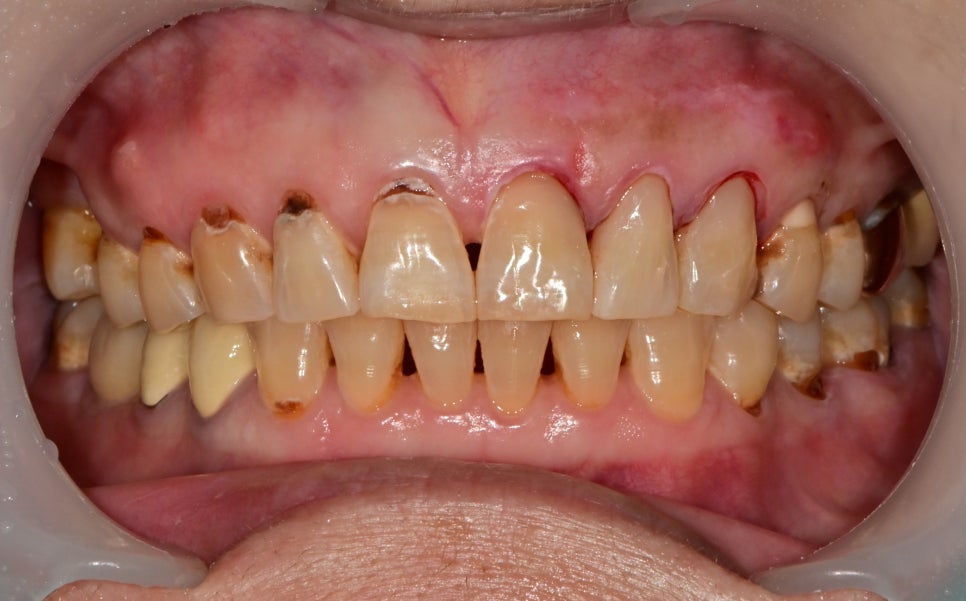

먼저 위쪽 절반을 먼저 치료한 날 사진입니다.

깊은 충치가 몇 군데 있었지만 신경안정을 위한 재료를 사용하여

신경치료 없이 레진으로만 색을 맞춰 자연스럽게 마무리했습니다.

치료전 사진과

잇몸치료와 레진 치료가 모두 끝나고 체크를 오셨을 때 사진입니다

내원 안 하셨던 기간 동안 다시 잇몸 주변 치태가 쌓여있어

다시 주변부를 깨끗하게 세척하고 레진 치료를 마무리할 수 있었습니다